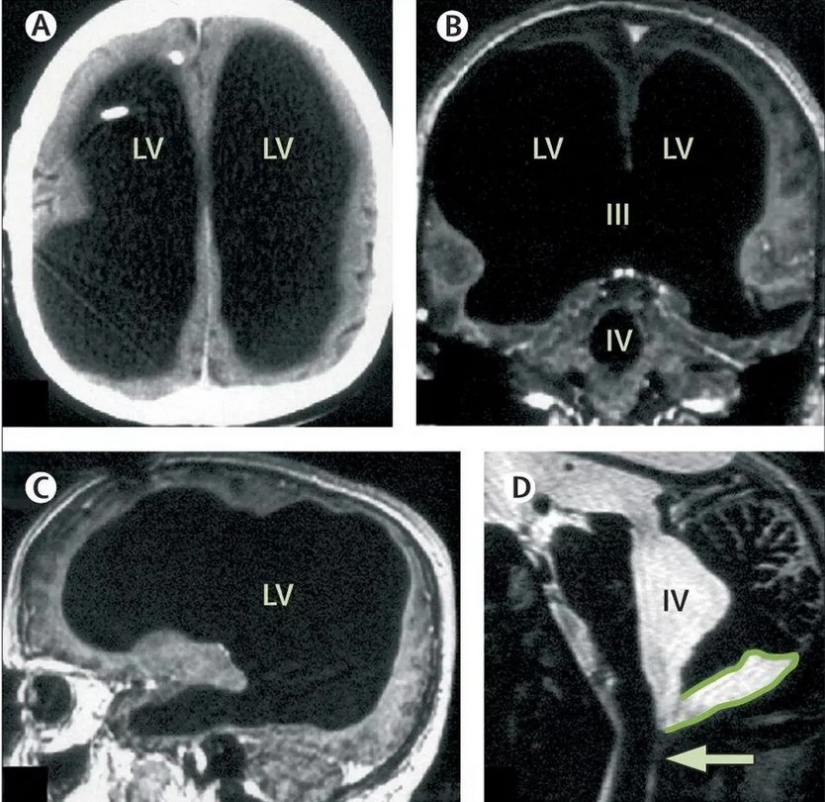

Sore legs were immediately forgotten, as it suddenly turned out that the patient was literally "empty in the head." An MRI scan showed that Mathieu's skull was almost completely filled with fluid. Only a thin shell remained of the brain. According to all the laws of nature, such a person could not live, much less work in a state institution, raise children and drive a car. The phenomenal man had an IQ of 75, which is not much, but within the normal range.

The patient never complained of head problems. Most likely, if it were not for the pain in his legs, Mathieu would have lived his whole life without knowing what a unique person he is. Specialists undertook to study the Frenchman and found the cause of his illness. His brain was slowly deteriorating over the course of 30 years, and liquid took its place. This process is called hydrocephalus or dropsy of the brain.

Mathieu contracted hydrocephalus in early childhood. Until the age of 14, he walked with a special shunt in his skull through which fluid could be drained. Then the device was removed, as it was considered that the guy had outgrown and recovered. And in fact, the disease began to pass secretly. Fluid accumulated in the skull, and the brain gradually collapsed. But for 30 years this did not affect the well-being of the man. The doctors shrug their shoulders, because they don’t know how to help Mathieu and whether he needs help at all. For now, they just continue to rid him of the fluid accumulating in his head.